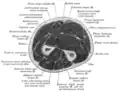

Cross-section through the middle of upper arm

Cross-section through the middle of the forearm